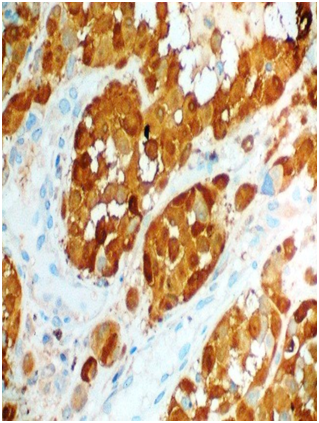

A 53-year-old female presented with one-month history of gross hematuria and increased frequency of urination. There was no past history of calculus. She did not have any medical comorbidities. She underwent hysterectomy after last childbirth at the age of 40 years. General physical examination and routine blood investigations were normal. CECT scan of whole abdomen showed 4.4x3.7x2 cm polypoid enhancing mass in urinary bladder with bladder wall thickening. Cystoscopy revealed blackish solitary papillary growth near bladder neck from 10 o’clock to 2 o’ clock position. A transurethral resection of the lesion was performed including deep muscular layers of the bladder wall. The respected specimen examination showed pigmented melanocytes infiltrating sub epithelial tissue below the transitional epithelium (Figure 1). Margins of resection were free, however, base was involved. Atypical melanocytes were seen at the margins of the tumor. Immunohistochemical study showed that tumor cells were positive for S-100 (Figure 2) and HMB-45 (Figure 3). They were negative for cytokeratin and SMA. Dermatologic, ophthalmologic, otorhinolaryngologic and proctologic evaluations were negative. Upper gastrointestinal endoscopy and colonoscopy were negative. Abdomen, chest and brain CT scans were negative. Bone scan was negative. These findings were consistent with primary malignant melanoma of urinary bladder. After thorough review of published scientific literature, we suggested radical cystectomy as the therapeutic option. The patient declined any further treatment so was given only symptomatic & supportive treatment. Nine months later, she presented with hematuria and back pain. PET-CT showed increased uptake in lumbosacral vertebrae and liver, suggestive of metastases. She was advised palliative radiotherapy to the painful bone metastases and continued to receive palliative care. She succumbed to complications caused by widespread metastases fourteen months after the diagnosis.

Figure 2 S-100: Cytoplasmic positivity in malignant melanocytes, (x45X).

Figure 3 HMB-45: Cytoplasmic positivity in malignant melanocytes, (x45X).